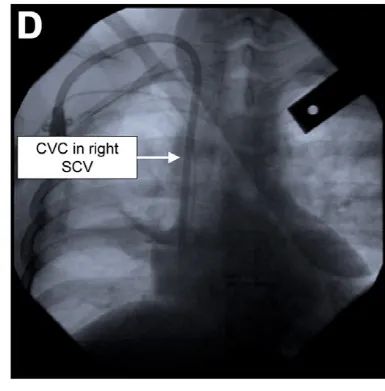

透视允许在扩张和引入CVCS之前对导丝进行实时可视化。当结合对比检查时,它可以用来描述静脉解剖,识别静脉狭窄或血栓的存在,以及诊断静脉外导线的放置(图D)。然而,并发症仍可能发生,特别是复杂的解剖结构,操作者缺乏经验或图像错误解释。在CVC放置过程中使用透视的证据有限,但国际社会指南建议将其作为替代技术,并认为对放置右心辅助装置是必要的。